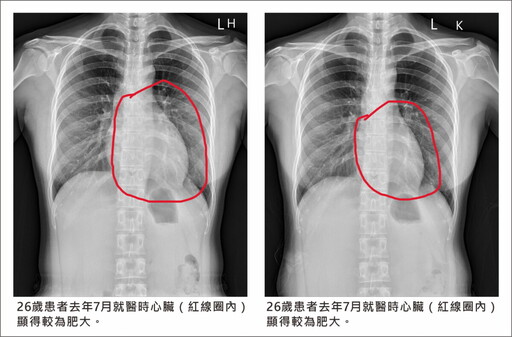

【創新聞 記者張溎壕/彰化報導】心臟衰竭也能逆轉!26歲李姓女子去年例行健檢時,X光片意外顯示心臟比正常大。就醫後發現左心室射出分率僅39%,已符合心臟衰竭定義。經10個月規律服藥與標準治療,心臟功能恢復正常,左心室射出分率提升至59%,接近健康標準。

▲26歲女子例行健檢發現心臟比常人大,左心室射出分率僅39%,接受員榮醫院心臟內科陳裕峰醫師經10個月規律藥物及標準治療後,心臟功能恢復正常。(員榮醫院提供)

這名年輕女子去年健檢時,透過X光片發現心臟比一般人稍大,便前往員榮醫院心臟內科就診,心臟內科陳裕峰醫師今(15)日表示,檢查結果顯示她左心室射出分率只有39%,正常應該至少50%以上,甚至60%以上才算理想,且心臟瓣膜出現較嚴重逆流,符合心臟衰竭標準。

▲26歲女子例行健檢發現心臟比常人大,左心室射出分率僅39%,接受員榮醫院心臟內科陳裕峰醫師經10個月規律藥物及標準治療後,心臟功能恢復正常。(員榮醫院提供)

在陳裕峰醫師的指導下,患者開始規律服藥,並接受心臟衰竭標準治療。經過10個月治療,心臟大小已恢復正常,左心室射出分率也從39%大幅提升至59%,接近正常值。陳醫師指出,心臟衰竭患者除了服藥,也可透過EECP(增強型體外反搏治療)改善心臟功能。